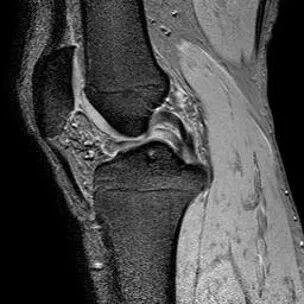

1、纵行撕裂2、撕裂方向和半月板长轴方向平行3、垂直或斜行的III级高信号

(半月板纵行撕裂)